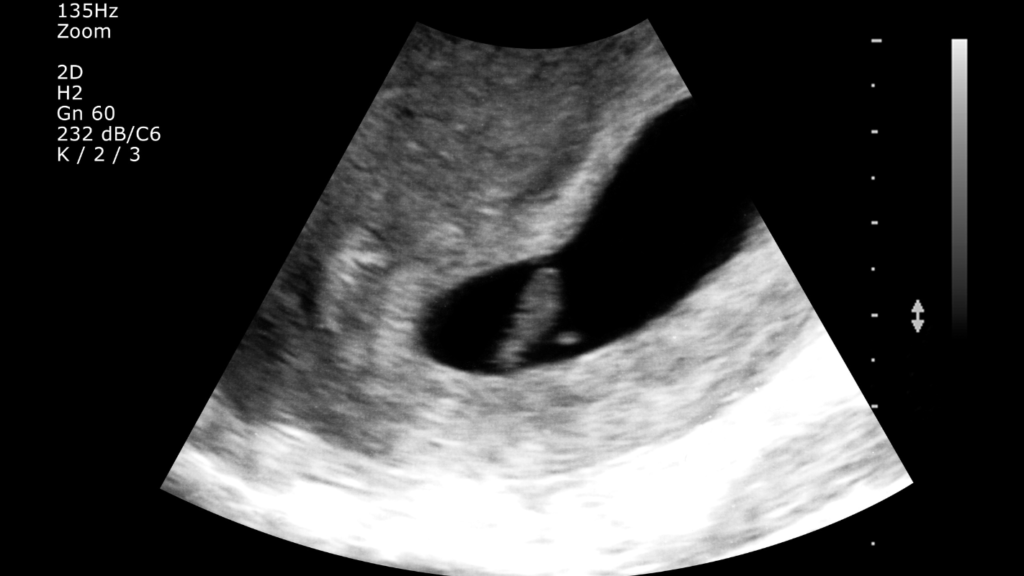

يعتبر ظهور اعراض الحمل من الأمور التي تختلف من شخص لآخر حيث منهم من تبدأ لديه الأعراض منذ بداية التزاوج ومن من يظهر بعدها بأكثر من أسبوع وبين هؤلاء وهؤلاء تعتبر أدق طريقة لاكتشاف الحمل هي عمل تحليل حمل في المختبر حيث يكشف هذا الاختبار عن وجود هرمون الحمل في البول والدم وذلك بعد مرور ما يقرب من عشرة أيام من إخصاب البويضة، أو من خلال استخدام اختبار الحمل المنزلي الذي يتم باستخدام البول، أو الذهاب إلى الطبيب وعمل فحص السونار.

يعتبر معرفة جنس الجنين واحد من أكثر الأمور التي تشغل بال الكثيرين منذ بداية الأسبوع الأول في الحمل، وتعتبر أدق طريقة للكشف عن جنس الجنين هي عمل سونار الذي يعمل بالموجات فوق الصوتية ويفضل أن يتم ذلك في الأسبوع العشرين من الحمل وذلك حتى يتمكن الطبيب من معرفة جنس الجنين حيث في هذه الفترة تكون قد اكتمل تكوين الأعضاء التناسلية الخاصة بكلاً من الذكر والأنثى وبالتالي يمكن التفريق بينهما.

كما يمكن أيضاً معرفة جنس الجنين باستخدام السونار ثلاثي الأبعاد ولكن هذا ينصح استخدامه في الأسبوع الثلاثين من الحمل وذلك لأن في هذه الفترة تكون قد تكونت طبقة من الدهون تخت جلد الطفل تساعد في توضيح الرؤية في السونار على عكس قبل هذه الفترة لا يظهر سوى العظام وبالتالي لا يمكن التحديد إذا كان المولود ذكر أم أنثى باستخدام هذا النوع من السونار.